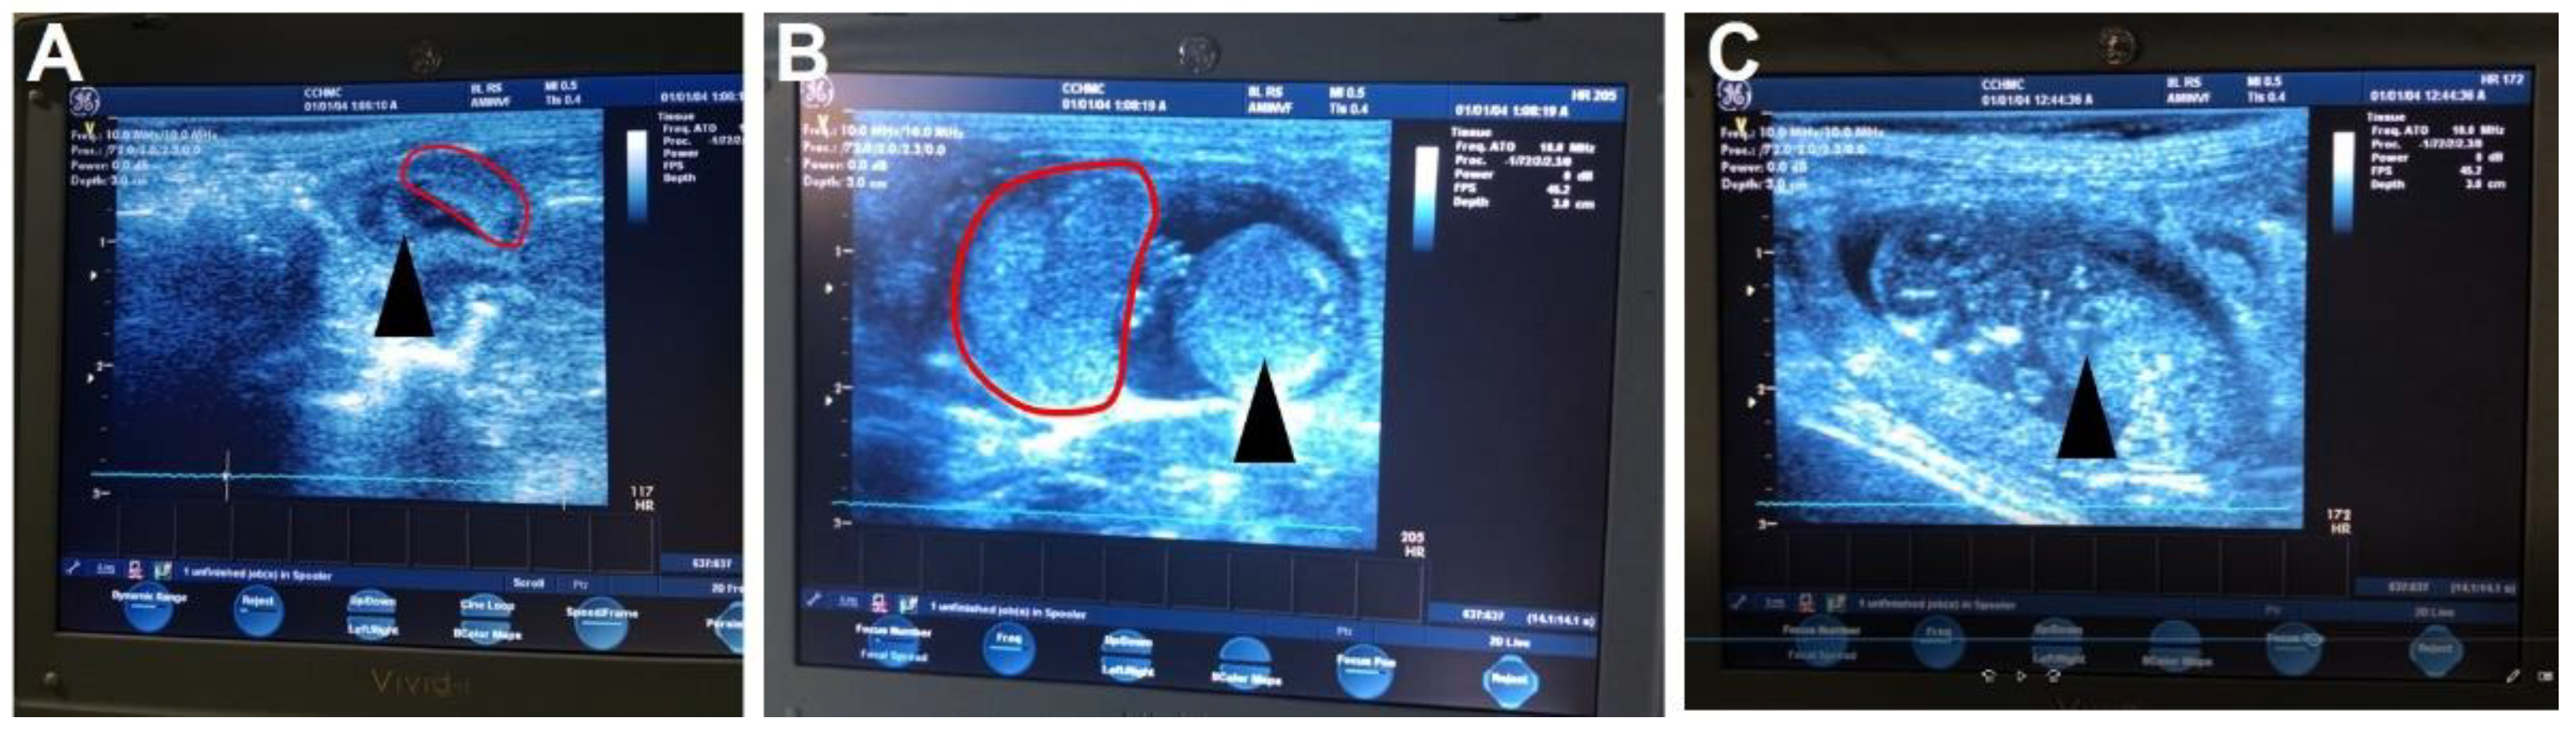

3.3. Ultrasound Pregnancy Confirmation

- Ultrasound pregnancy confirmation can be performed without anesthesia [20] between GD21-30.

- Whilst carefully restraining the guinea pig, shave the female guinea pig’s lower abdomen.

- Set the ultrasound to a depth between 6 and 10 cm and a frequency between 8 and 10 MHz.

- Place enough ultrasound coupling gel on the end of the ultrasound probe to cover the probe and perform the ultrasound. Scan from the cervix up to each uterine horn until a conceptus is found. Multiple conceptuses may be observed, but only one is needed to confirm the pregnancy.

- Once the pregnancy is confirmed, return the animal to the group housing.